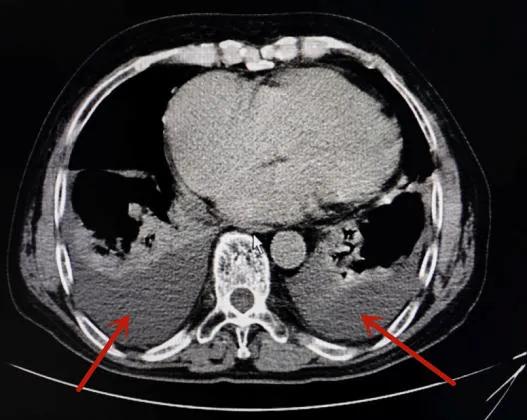

(双侧胸腔积液、心脏扩大)

询问病史得知,最近一个月来,李爷爷体力明显不如从前,步行100米都会喘气。医生立即为其完善胸腹部CT、心脏彩超及心电图等检查,结果显示李爷爷双侧胸腔有积液,心脏扩大,并伴有左心室舒张功能减退、心房颤动等,被诊断为心衰、房颤。